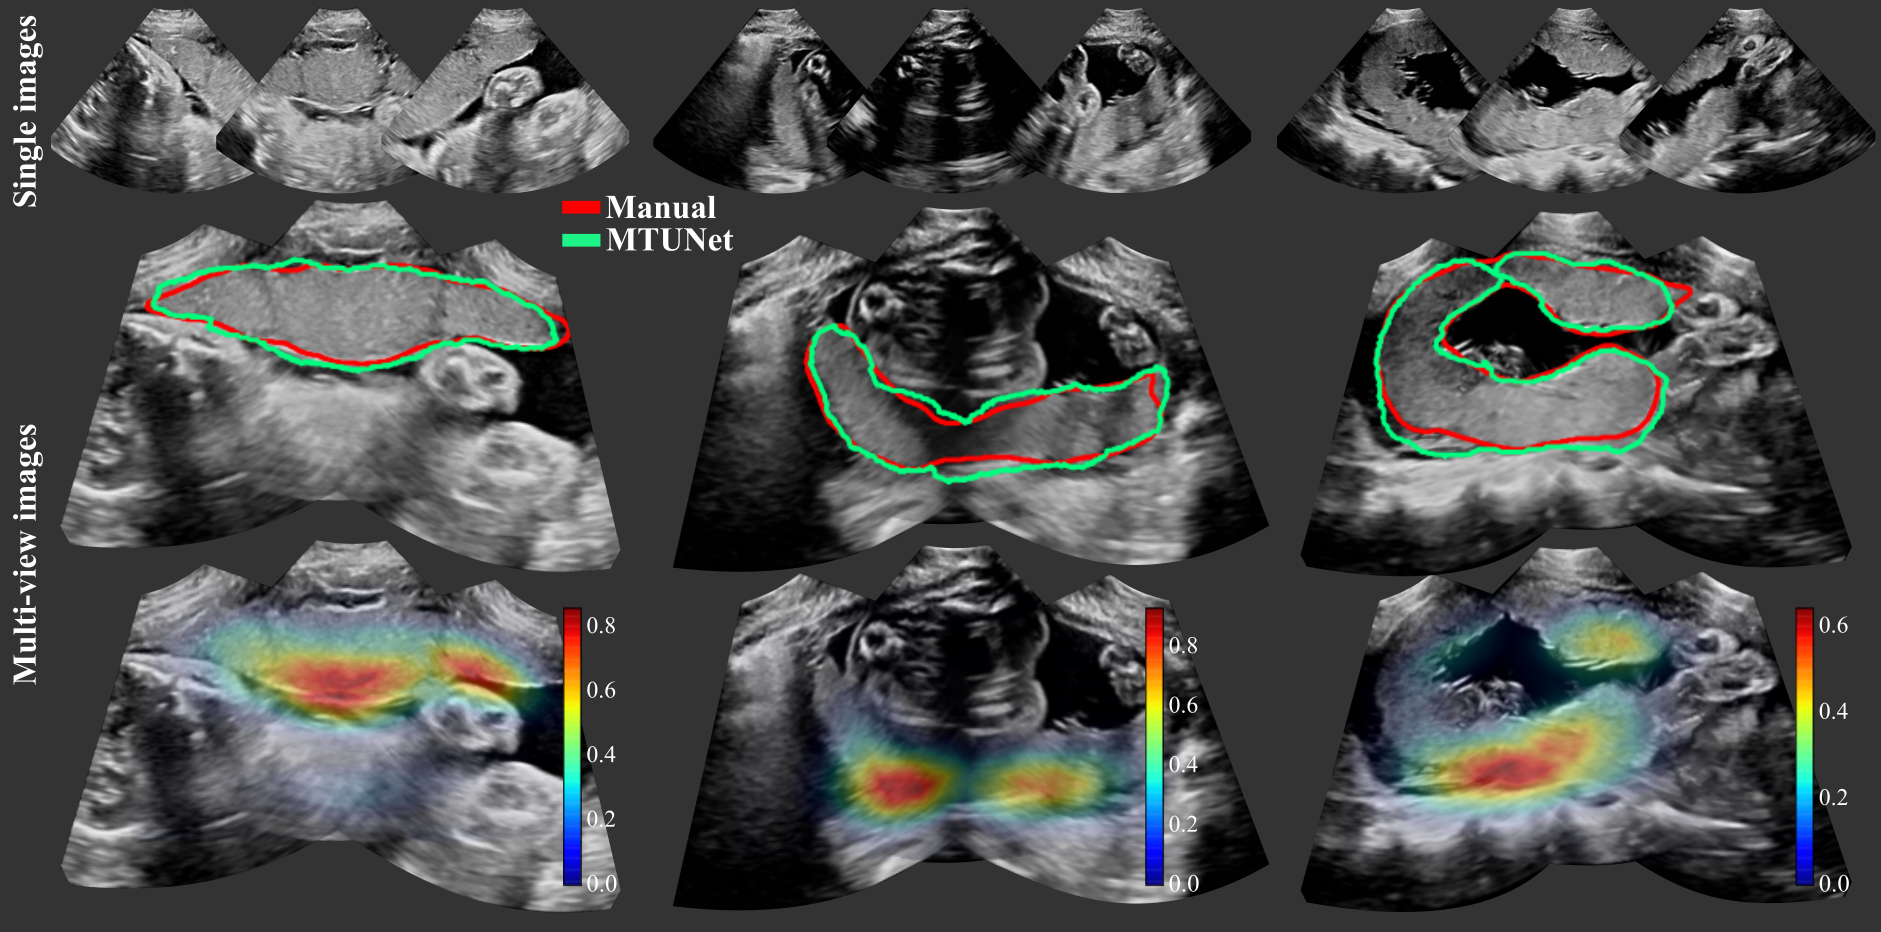

Examplary multi-view images are shown in Fig. 5 with corresponding placenta segmentations with MTUNet and combined attention maps. The placenta is better visualized in the multi-view images with reduced image artifacts and an extended FoV. The multi-task model MTUNet provides an accurate segmentation and the combined attention maps localize well the placenta. Further examples of multi-view images with corresponding segmentations can be found in Fig. 12 in the appendix.